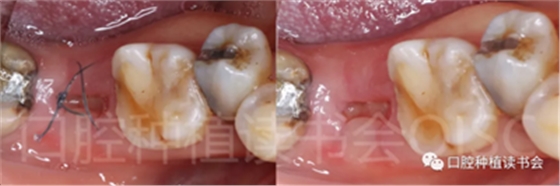

5.3.7 術后1周拆線,47位點愈合良好(圖20),患者術后未訴疼痛不適。

圖20 不翻瓣即刻種植手術可有效減小術后不適。

5.3.8 術后第3周,拔除48近中傾斜阻生智齒,觀察47位點愈合良好(圖21)。

圖21 拔除傾斜阻生的48,利于47后期的修復。